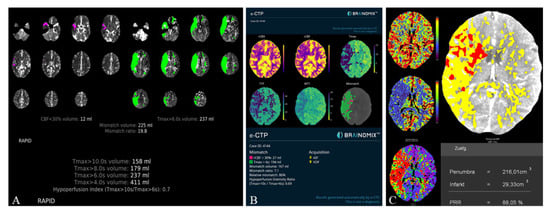

2.1.3. Automated CT Perfusion Software